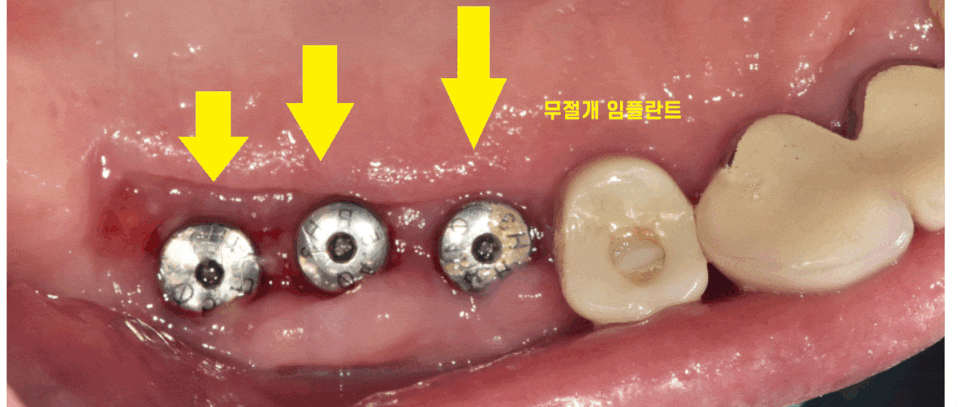

천호동 치과에서는 90% 이상의 수술을

무절개로 시행합니다.

잇몸에 작은 구멍을 내어

천호동 임플란트를 식립하는 것인데요.

수술 시간이 짧다

감염 , 출혈, 통증이 적다

환자분들께 좋기 때문에

천호동 임플란트 무절개 방식으로 적극 진행합니다.